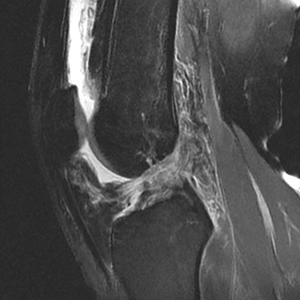

Figure 2

- Magnetic Resonance Imaging (MRI): MRI is the gold standard with imaging for diagnosing ACL tears. MRI provides a detailed view into the soft tissues of the knee including ligaments, cartilage, and menisci. This is important because ACL tears are often associated with injuries to other structures. Figure 2 shows an ACL tear on the MRI.